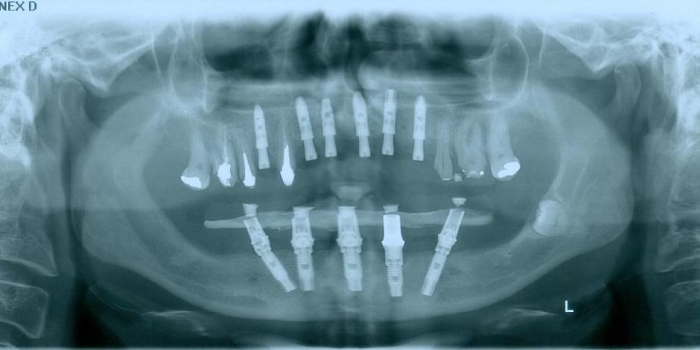

Raio - x Próteses Definitivas em Outubro de 2016  - Clínica Cliniface

Raio - x Próteses Definitivas em Outubro de 2016